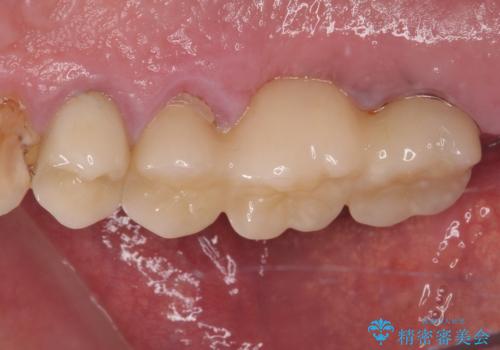

割れてしまった奥歯 抜歯即時埋入インプラントによる短期間治療

- 6ヶ月

- 5-10回

術後にインプラントの安定値を測定し、十分な値が達成された後、速やかにセラミッククラウンにて補綴治療を行うこととしました。

強い咬合力により歯根破折を繰り返しているため、即日荷重あるいは早期荷重による他の歯への負担を軽減することが重要となります。

抜歯即時埋入インプラントは、咬合力によるトラブルを回避する、非常に有用な手段となります。